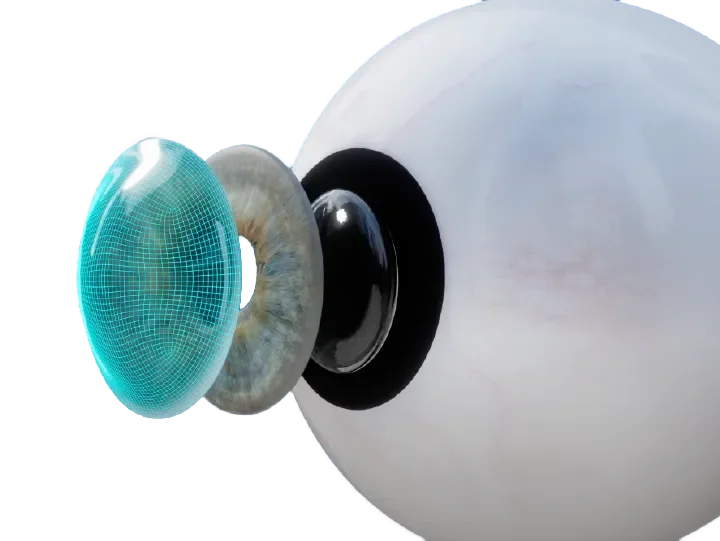

Scleral lenses are large diameter gas-permeable contact lens devices.

Rather than sitting directly on the eye like a traditional soft lens, scleral lenses only touch the sclera (the white part of the eye) and vault entirely over the cornea (the front of your eye - a clear layer of tissue that covers your iris, pupil and lens). This vault - the space between the contact lens and your cornea - is filled with fluid and creates a new, perfect focusing surface.

By vaulting over the eye with fluid, we are able to manage complicated eye conditions such as astigmatism, keratoconus, corneal transplants, severe dry eye, corneal scarring, LASIK complications and more. These lenses can be life changing.

Types of Scleral Lenses

Standard Scleral Lenses

For the straightforward case with no need for extra customizations.

Custom Scleral Lenses

When customizations are needed or when conventionals fall short. Includes scan-based, freeform, and EyeFitPro (impression molding). 40,000 data points are collected to create a custom fit lens.

Ultra Custom Scleral Lenses

For the ultimate precise fit and full customization options utilizing impression molding (EyePrintPro). 80,000 points of data are collected to create a truly unique scleral lens.